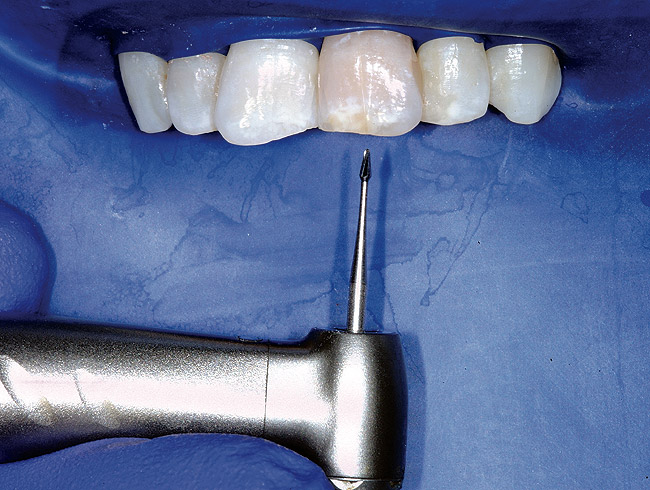

Single-tooth isolation does not give the clinician a good 3-dimensional feel for root anatomy and angulation. The problem is further compounded when there is a full crown present and the original anatomic landmarks are gone. The clamp can also impede handpiece orientation, which further steers the clinician astray. Additionally, the clamp blocks x-ray passage if the clinician chooses to pause and take a radiograph for access location and direction verification. Endodontists often report that they remove the rubber dam entirely for difficult calcified cases. This enables the clinician to develop a better feel for the three-dimensional procedure of canal discovery, and then replace the dam once the canal systems are safely discovered. The author finds that the quadrant dam offers the best of both worlds ( Figure 14).

The first step in the access for the calcified tooth is the establishment of the palatal–incisal notch ( Figure 15 and Figure 16). Once the area where the original pulp chamber was located has been accessed, it is advisable to take an orientation verification radiograph or multiple angled radiographs ( Figure 17). The palatal–incisal notch works in concert with the narrow shaft of the bur to perform important tasks. Similar to a surgical stint for implant drilling, the notch first stabilizes and directs the head of the bur by cradling the shaft. Secondly, it allows a more appropriate angulation—toward the incisal—of the back of the bur. Anatomy lessons have taught clinicians that the root and the crown of incisors are not parallel.